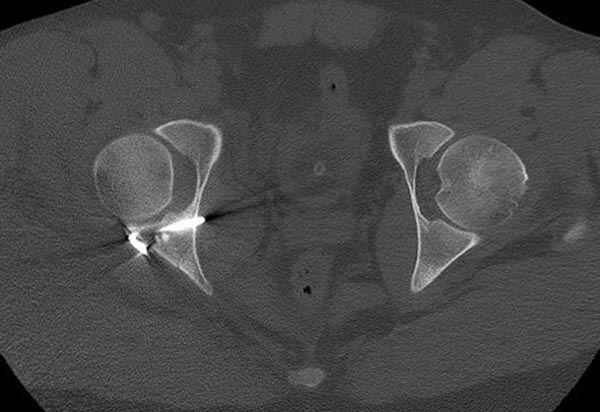

5:24 Рентгенограмма таза, вызывают врача ортопеда (снимок N1), его диагноз: закрытый переломо-вывих правого тазабедренного сустава, получает добро на закрытую репозицию в приемном отделении

N 2

Интраоперционные N5 косая запирательная и N6 подвздошный снимок

11:50 больной в послеоперационной, рентгенограмма N7, компьютерная томограмма в тот же день N8-10